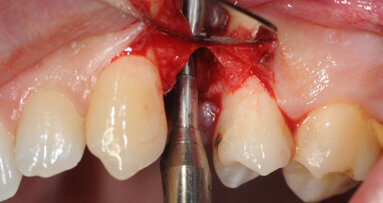

Immediate placement of implants into fresh extraction sockets has been shown to deliver good outcomes. The literature reports good implant survival rates, ...

Immediate implant placement is a well-recognised and successful treatment option after tooth extraction.[1, 2] Success rates for both immediate and ...

The placement of implants immediately after tooth extraction has proven to be a predictable treatment strategy with a very high success rate. Nevertheless, ...